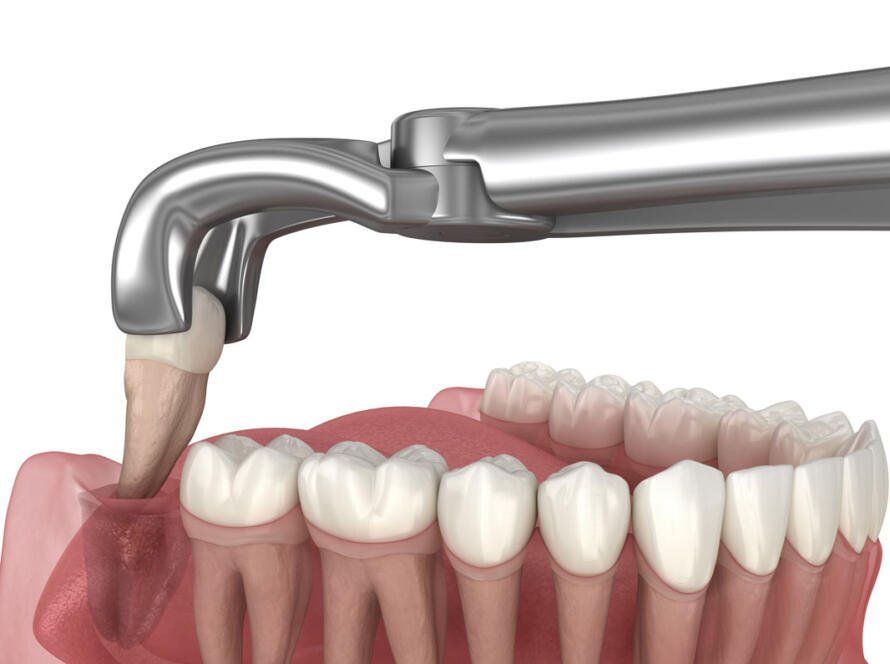

Master Your Wisdom Tooth Extraction Decision Wisdom tooth extraction resolves pain and prevents complications from problematic third molars. Wisdom tooth surgery safely removes impacted or misaligned teeth, restoring oral comfort. In New…